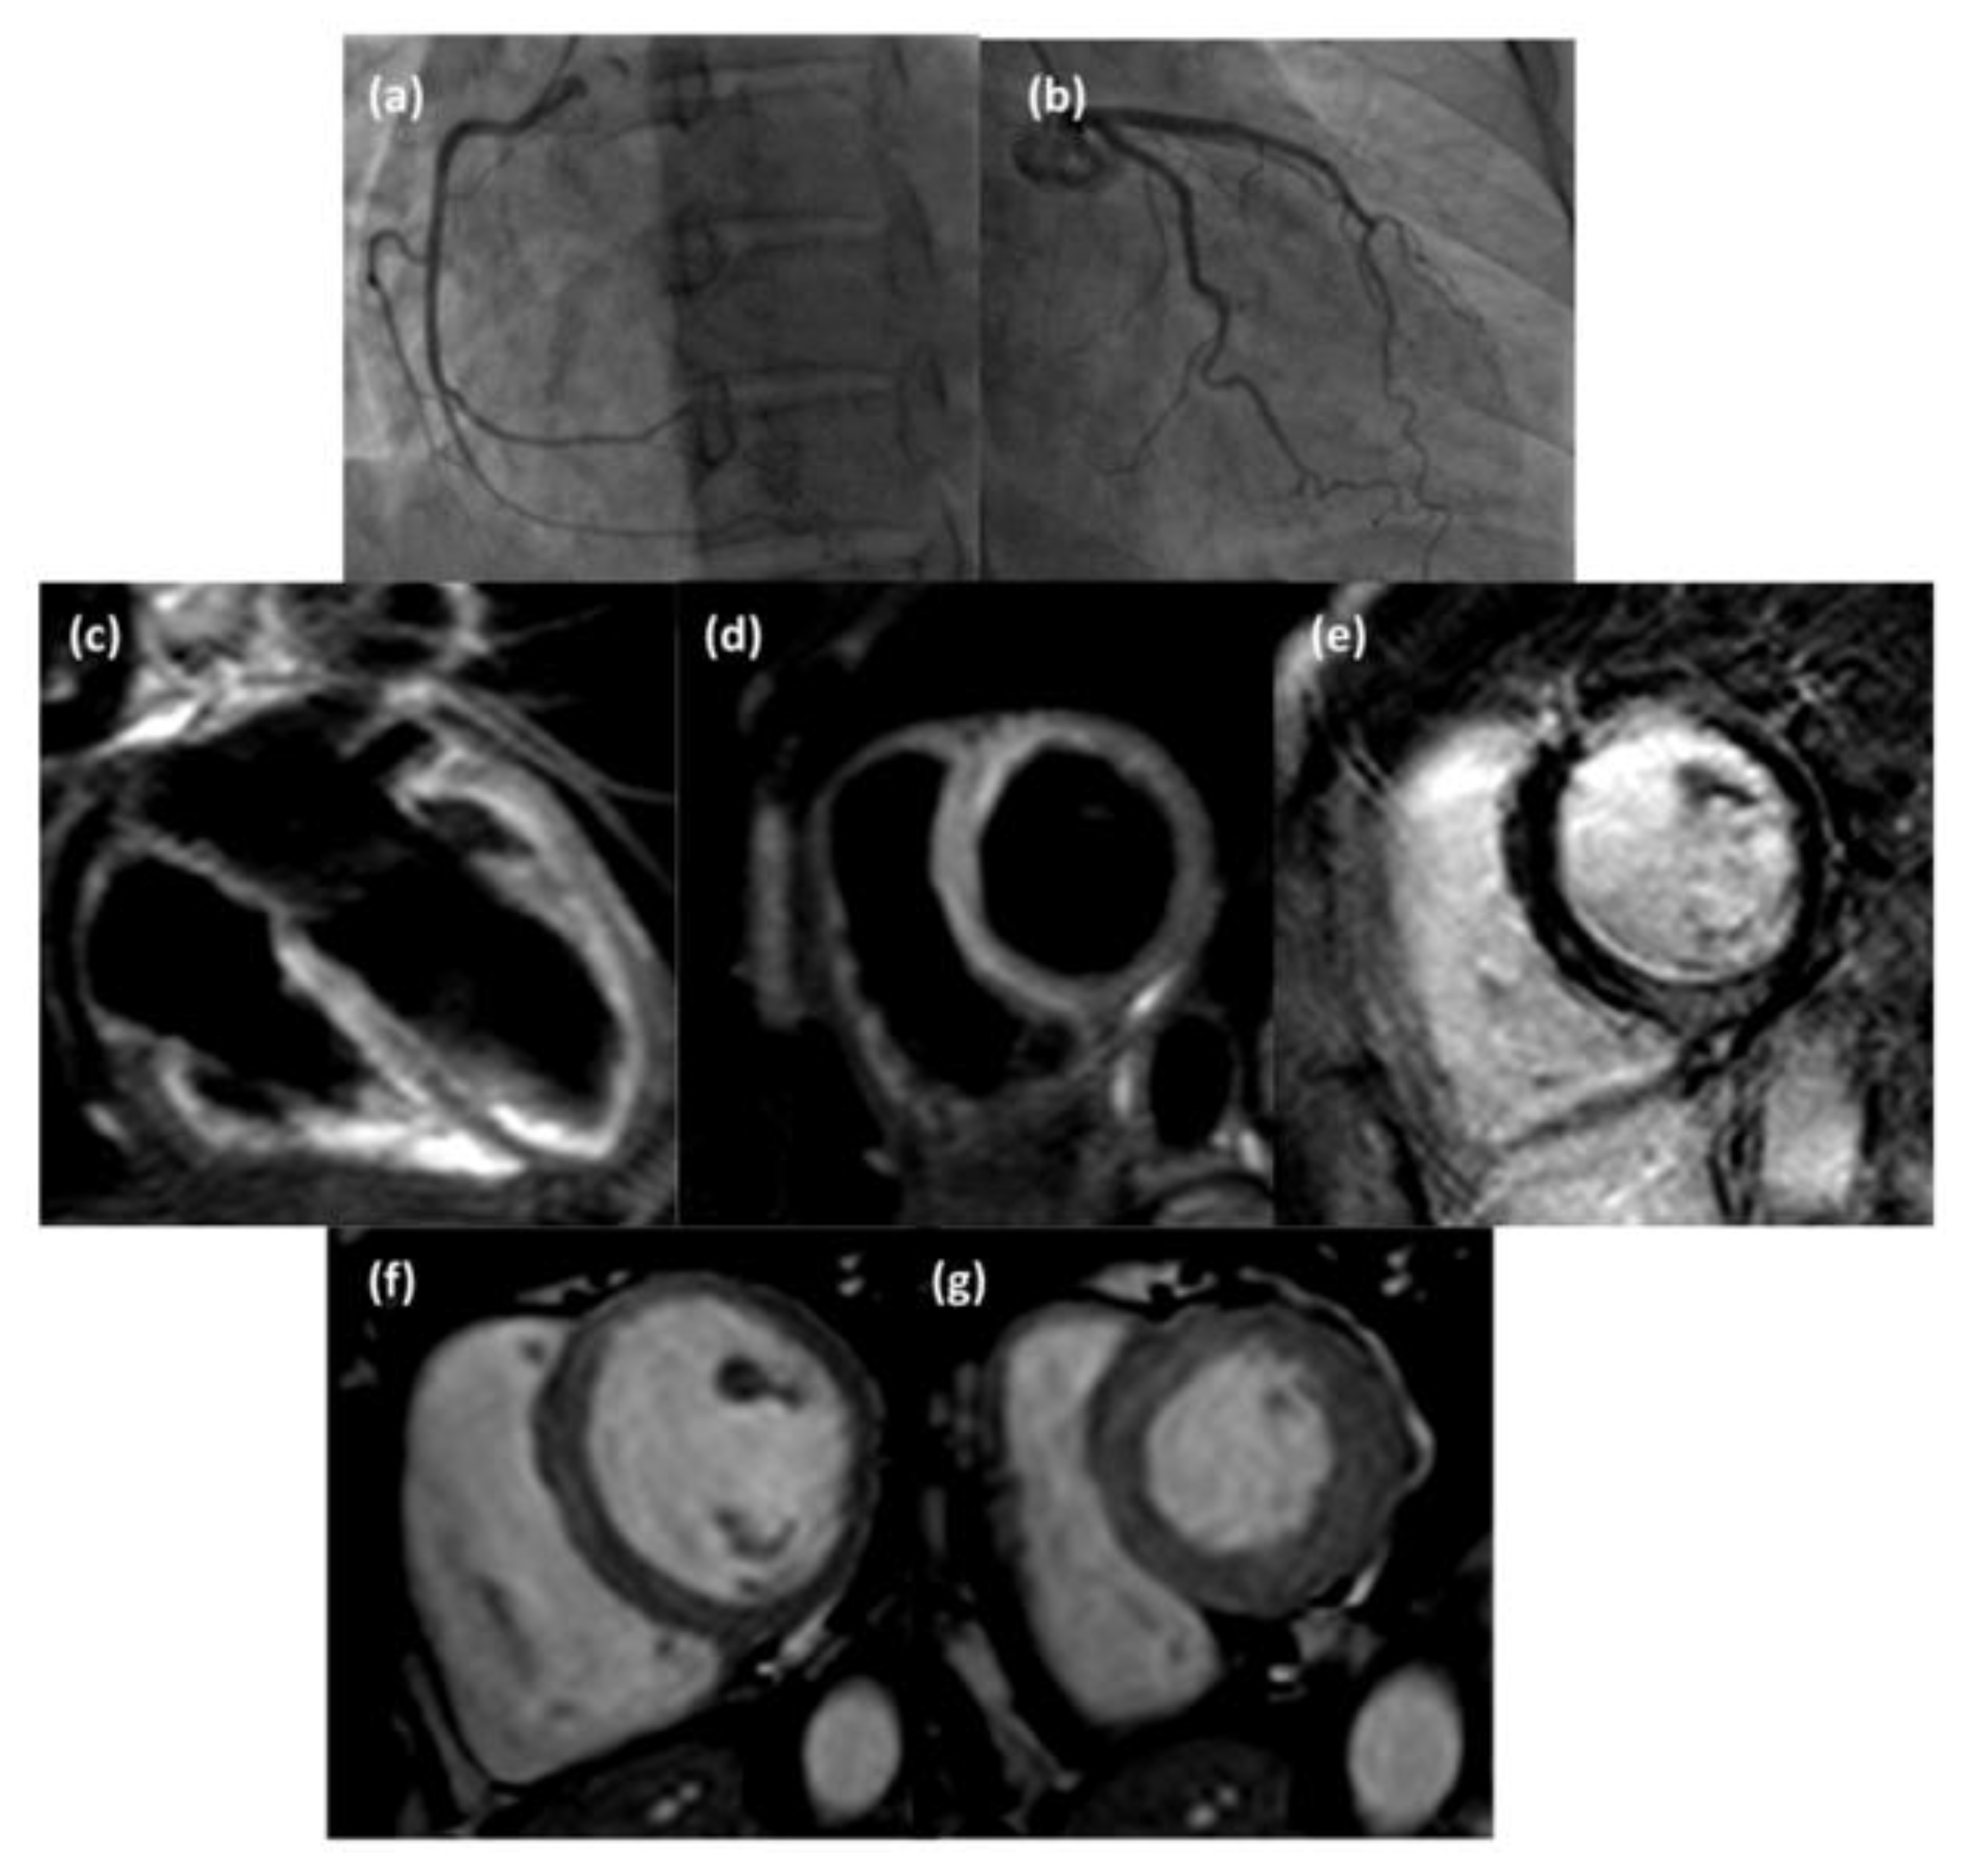

Figure 4.

Coronary angiography images (a,b) of a 48-year-old woman suspected of acute coronary syndrome that did not show hemodynamically significant stenosis; CMR examination revealed the presence of subepicardial-intramural edema (T2-weighted STIR 4-chamber view (c) and short axis view (d)) at the basal septum, intramural late gadolinium enhancement (inversion recovery T1-weighted short axis view, (e)) at the inferior septal wall, and slight mesocardial diastolic hyperemia at interventricular septum (cine steady-state free precession short axis view in diastol (f) and systole (g)).